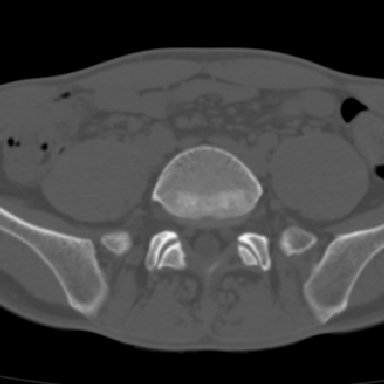

m 30 腰背部不适半年; 清晨时僵硬; 活动症状有所改善

强直性脊柱炎的早期改变!不仅表现为双侧骶髂关节,第5腰椎与骶椎间的关节突关节也有类似改变。

双侧骶髂关节下2/3关节面模糊,毛糙,髂骨侧可见小囊状骨质破坏区,骶髂关节间隙增宽(软骨破坏期)。支持早期强直性脊柱炎。

双侧骶髂关节下2/3关节面模糊、毛糙,可见小囊状骨质破坏区,呈虫咬状改变,周围可见增生硬化.支持强直性脊柱炎早期表现.